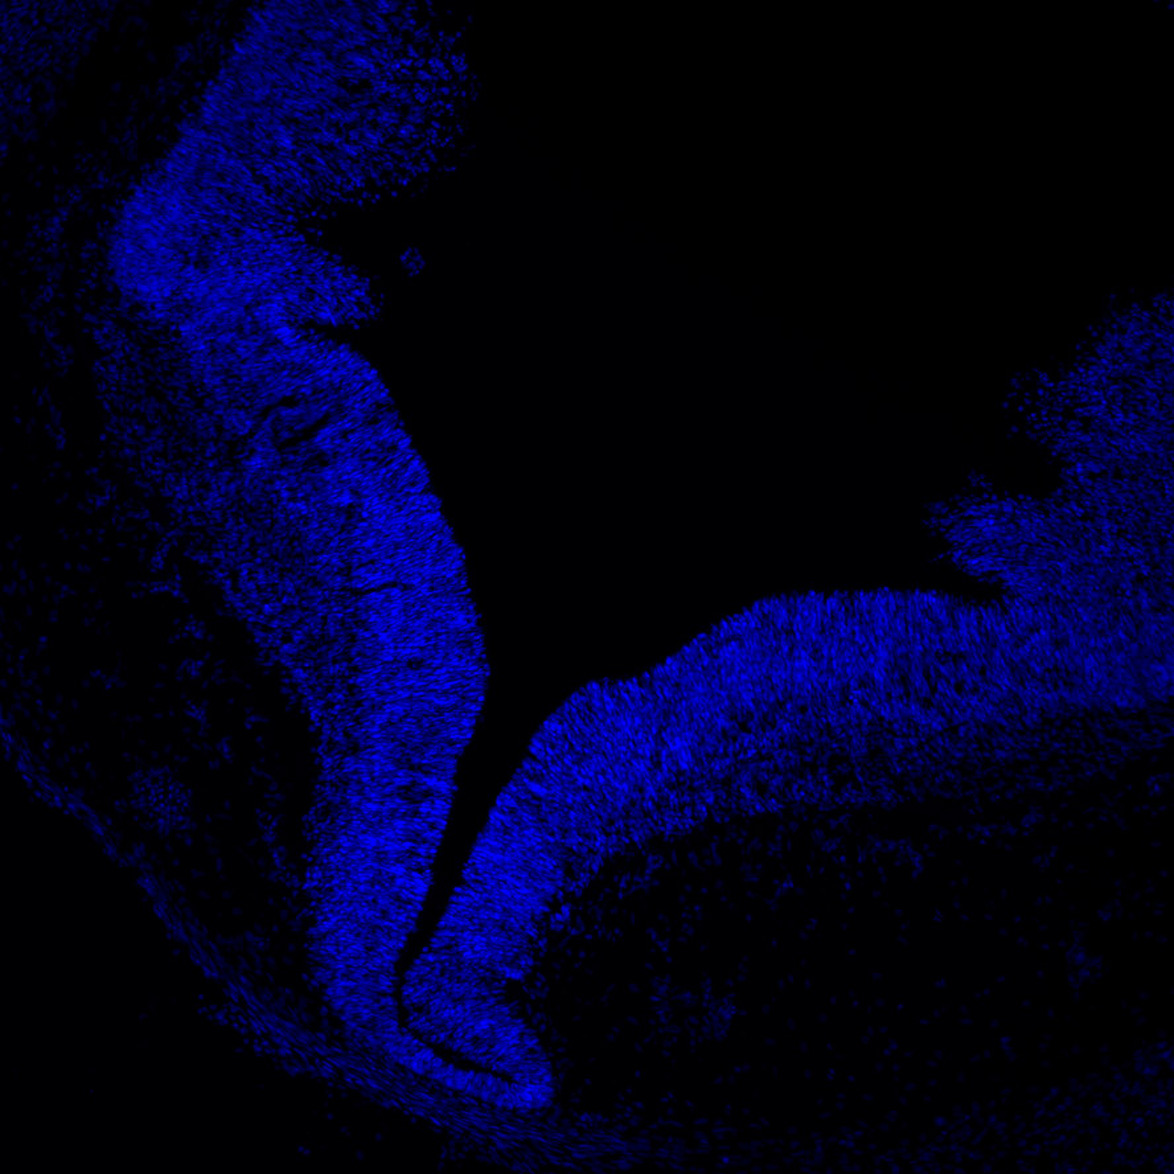

DAPI

7PCW human midbrain